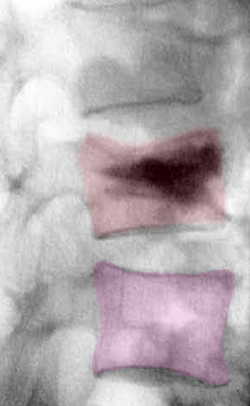

Κάταγμα 01 (φούξια) με μείωση του ύψους του σπονδύλου σε σύγκριση με τον υποκείμενο υγιή σπόνδυλο (μπλέ)(αριστερά). Κυφοπλαστική με ανάταξη του κατάγματος και επαναφορά του ύψους του σπονδύλου στο φυσιολογικό (δεξιά).